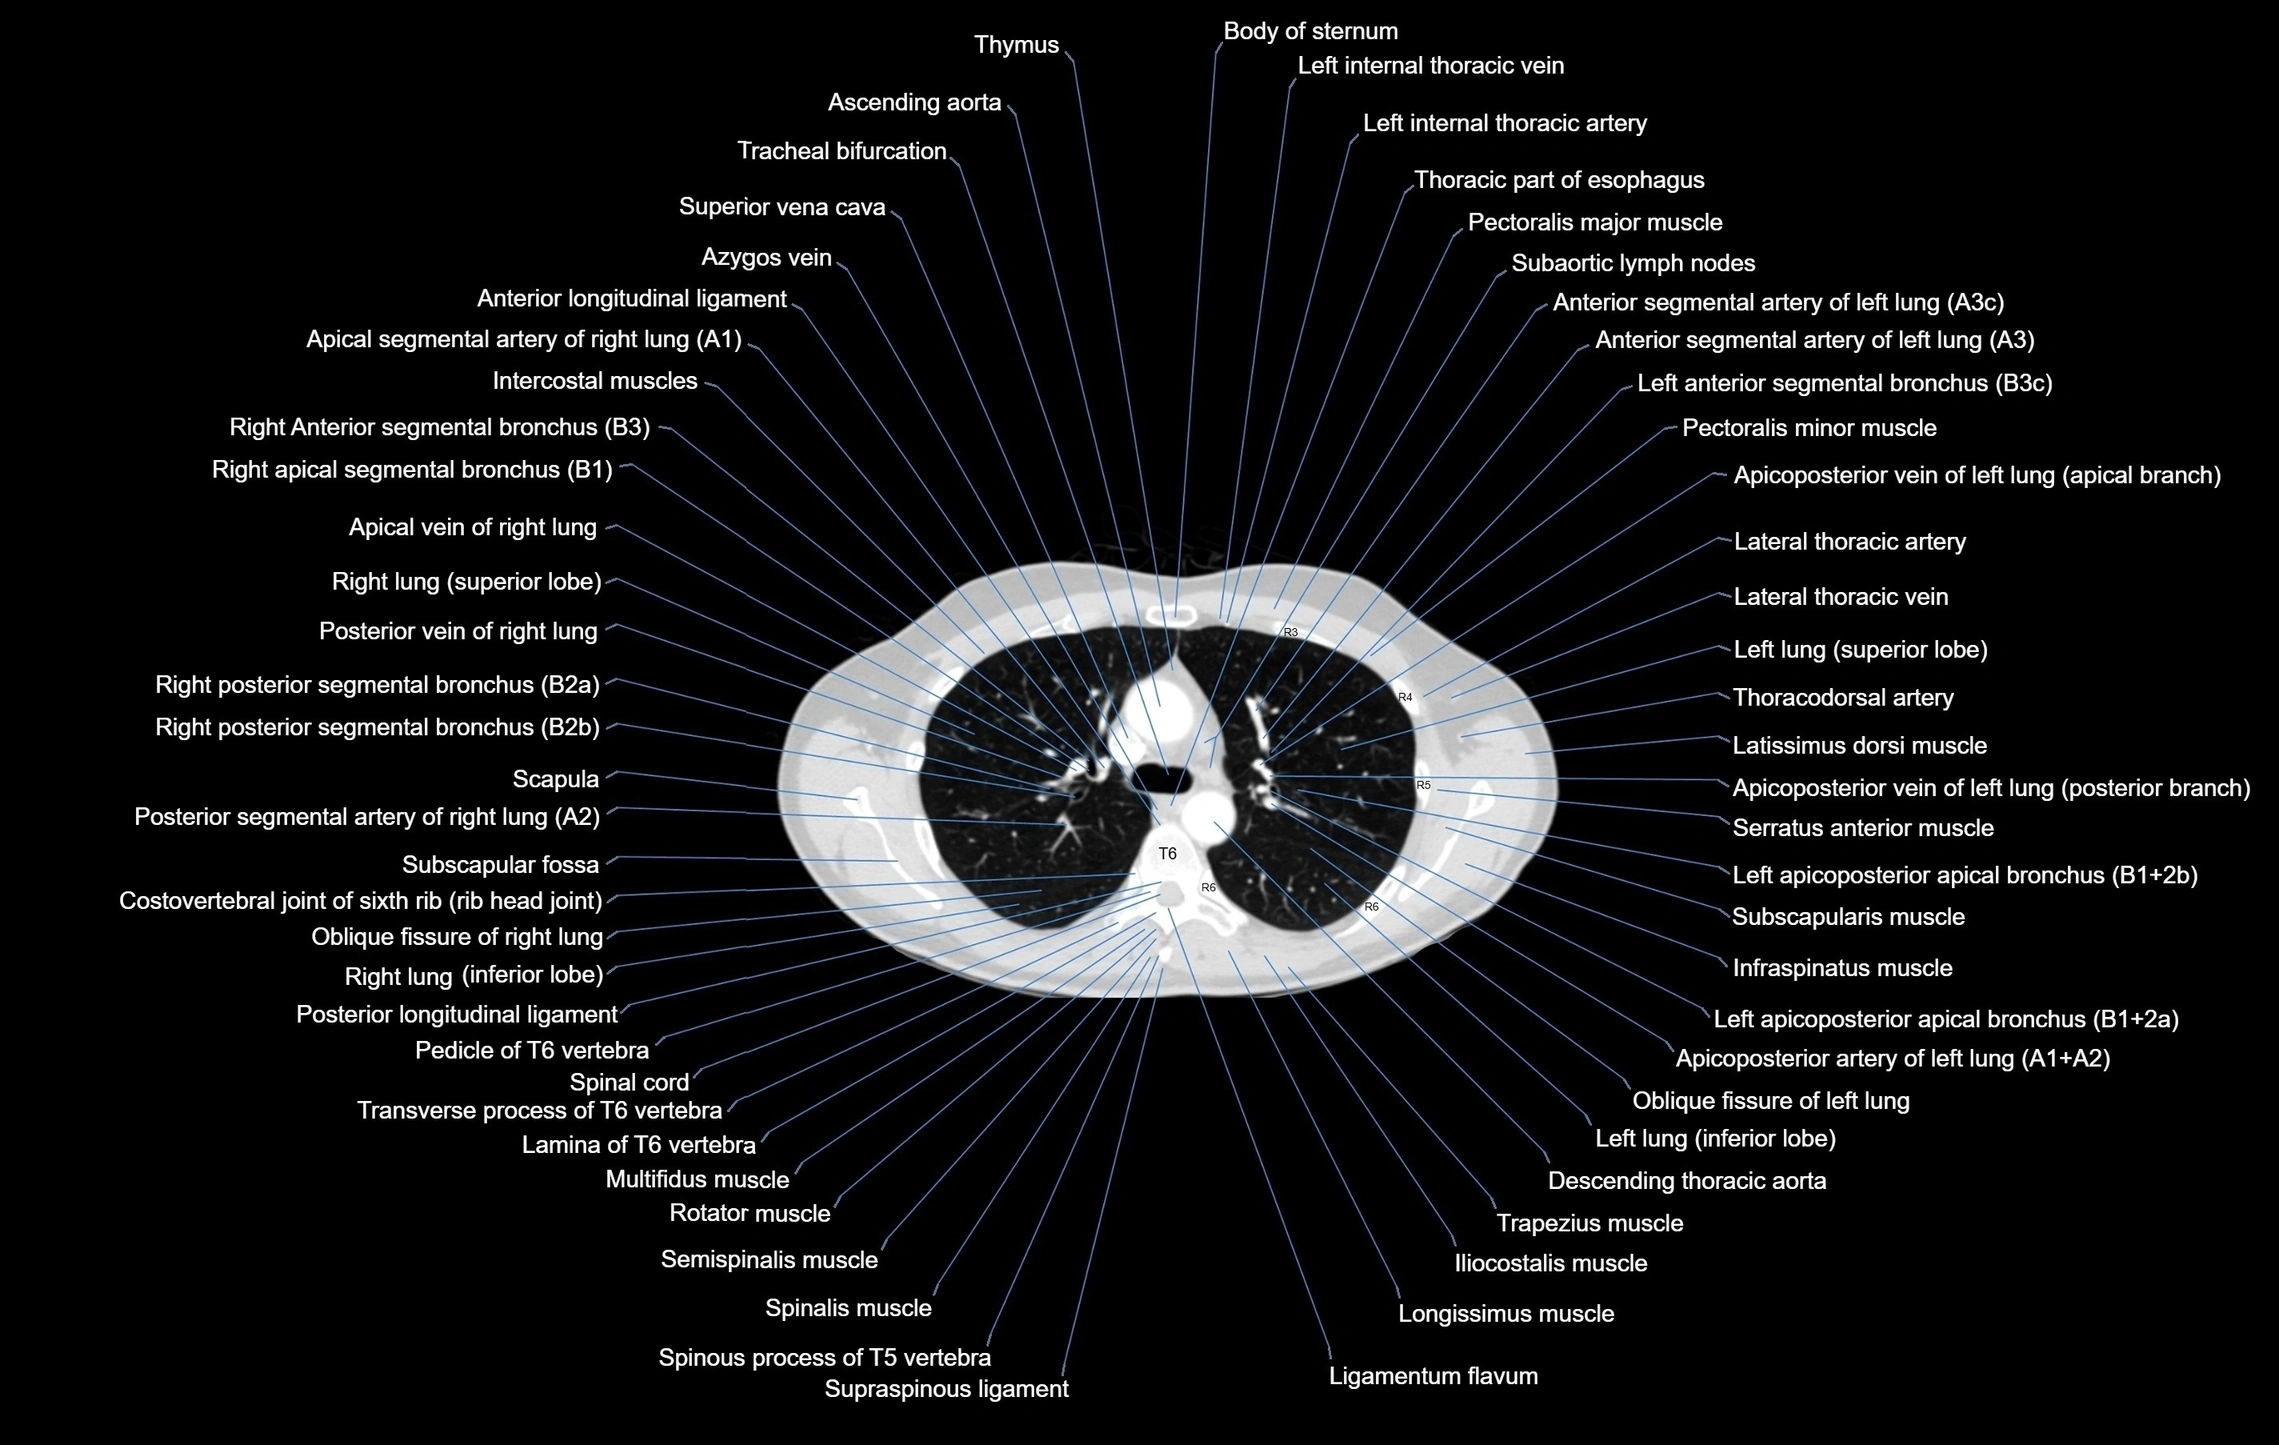

CT images